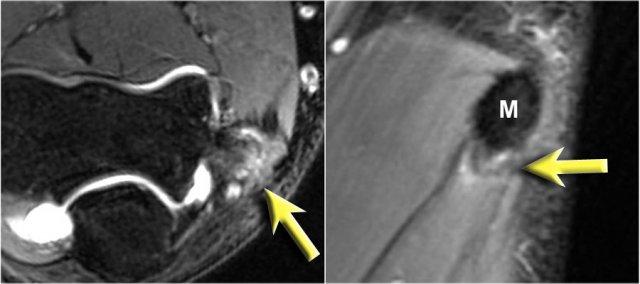

Arthrosis in valgus overload syndrome

Do quá tải valgus, có các lực cắt tác động lên phần sau-trong của khớp cánh tay-trụ.

Lưu ý tình trạng xơ cứng dưới sụn được thấy trên ảnh T1W (mũi tên đỏ).

Trên hình ảnh T2W có phù tủy xương dưới sụn và mất sụn khớp (mũi tên vàng).

Đây là hình ảnh của một vận động viên bóng chày 20 tuổi.

Trên các hình ảnh mặt phẳng coronal, bó trước của dây chằng UCL hiện rõ đẹp, nhưng lưu ý rằng có sự hình thành gai xương ở phần trong của khớp (mũi tên đỏ).

Khi chúng ta đi xa hơn về phía sau có một vùng nhỏ có tín hiệu thấp (mũi tên vàng), đây là một chỗ bong gân của một phần dây chằng bên trụ (UCL).

Khi quan sát trên lát cắt ngang (axial), chúng ta có thể nhận thấy sự hình thành gai xương khổng lồ.

Lưu ý rằng dây thần kinh trụ (mũi tên màu xanh) nằm cạnh các gai xương này và những bệnh nhân này có thể biểu hiện bệnh lý thần kinh trụ.